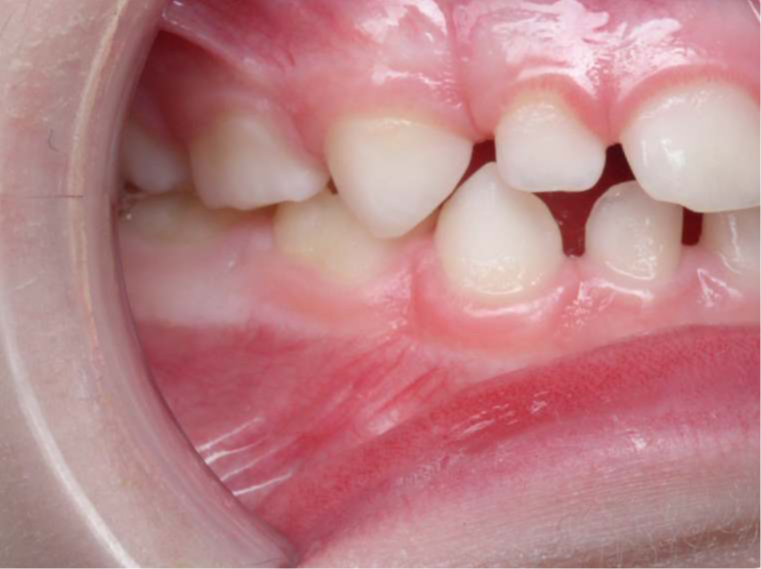

4.supraclusion inversé gauche 4 ans

inversion des dents postérieur coté gauche